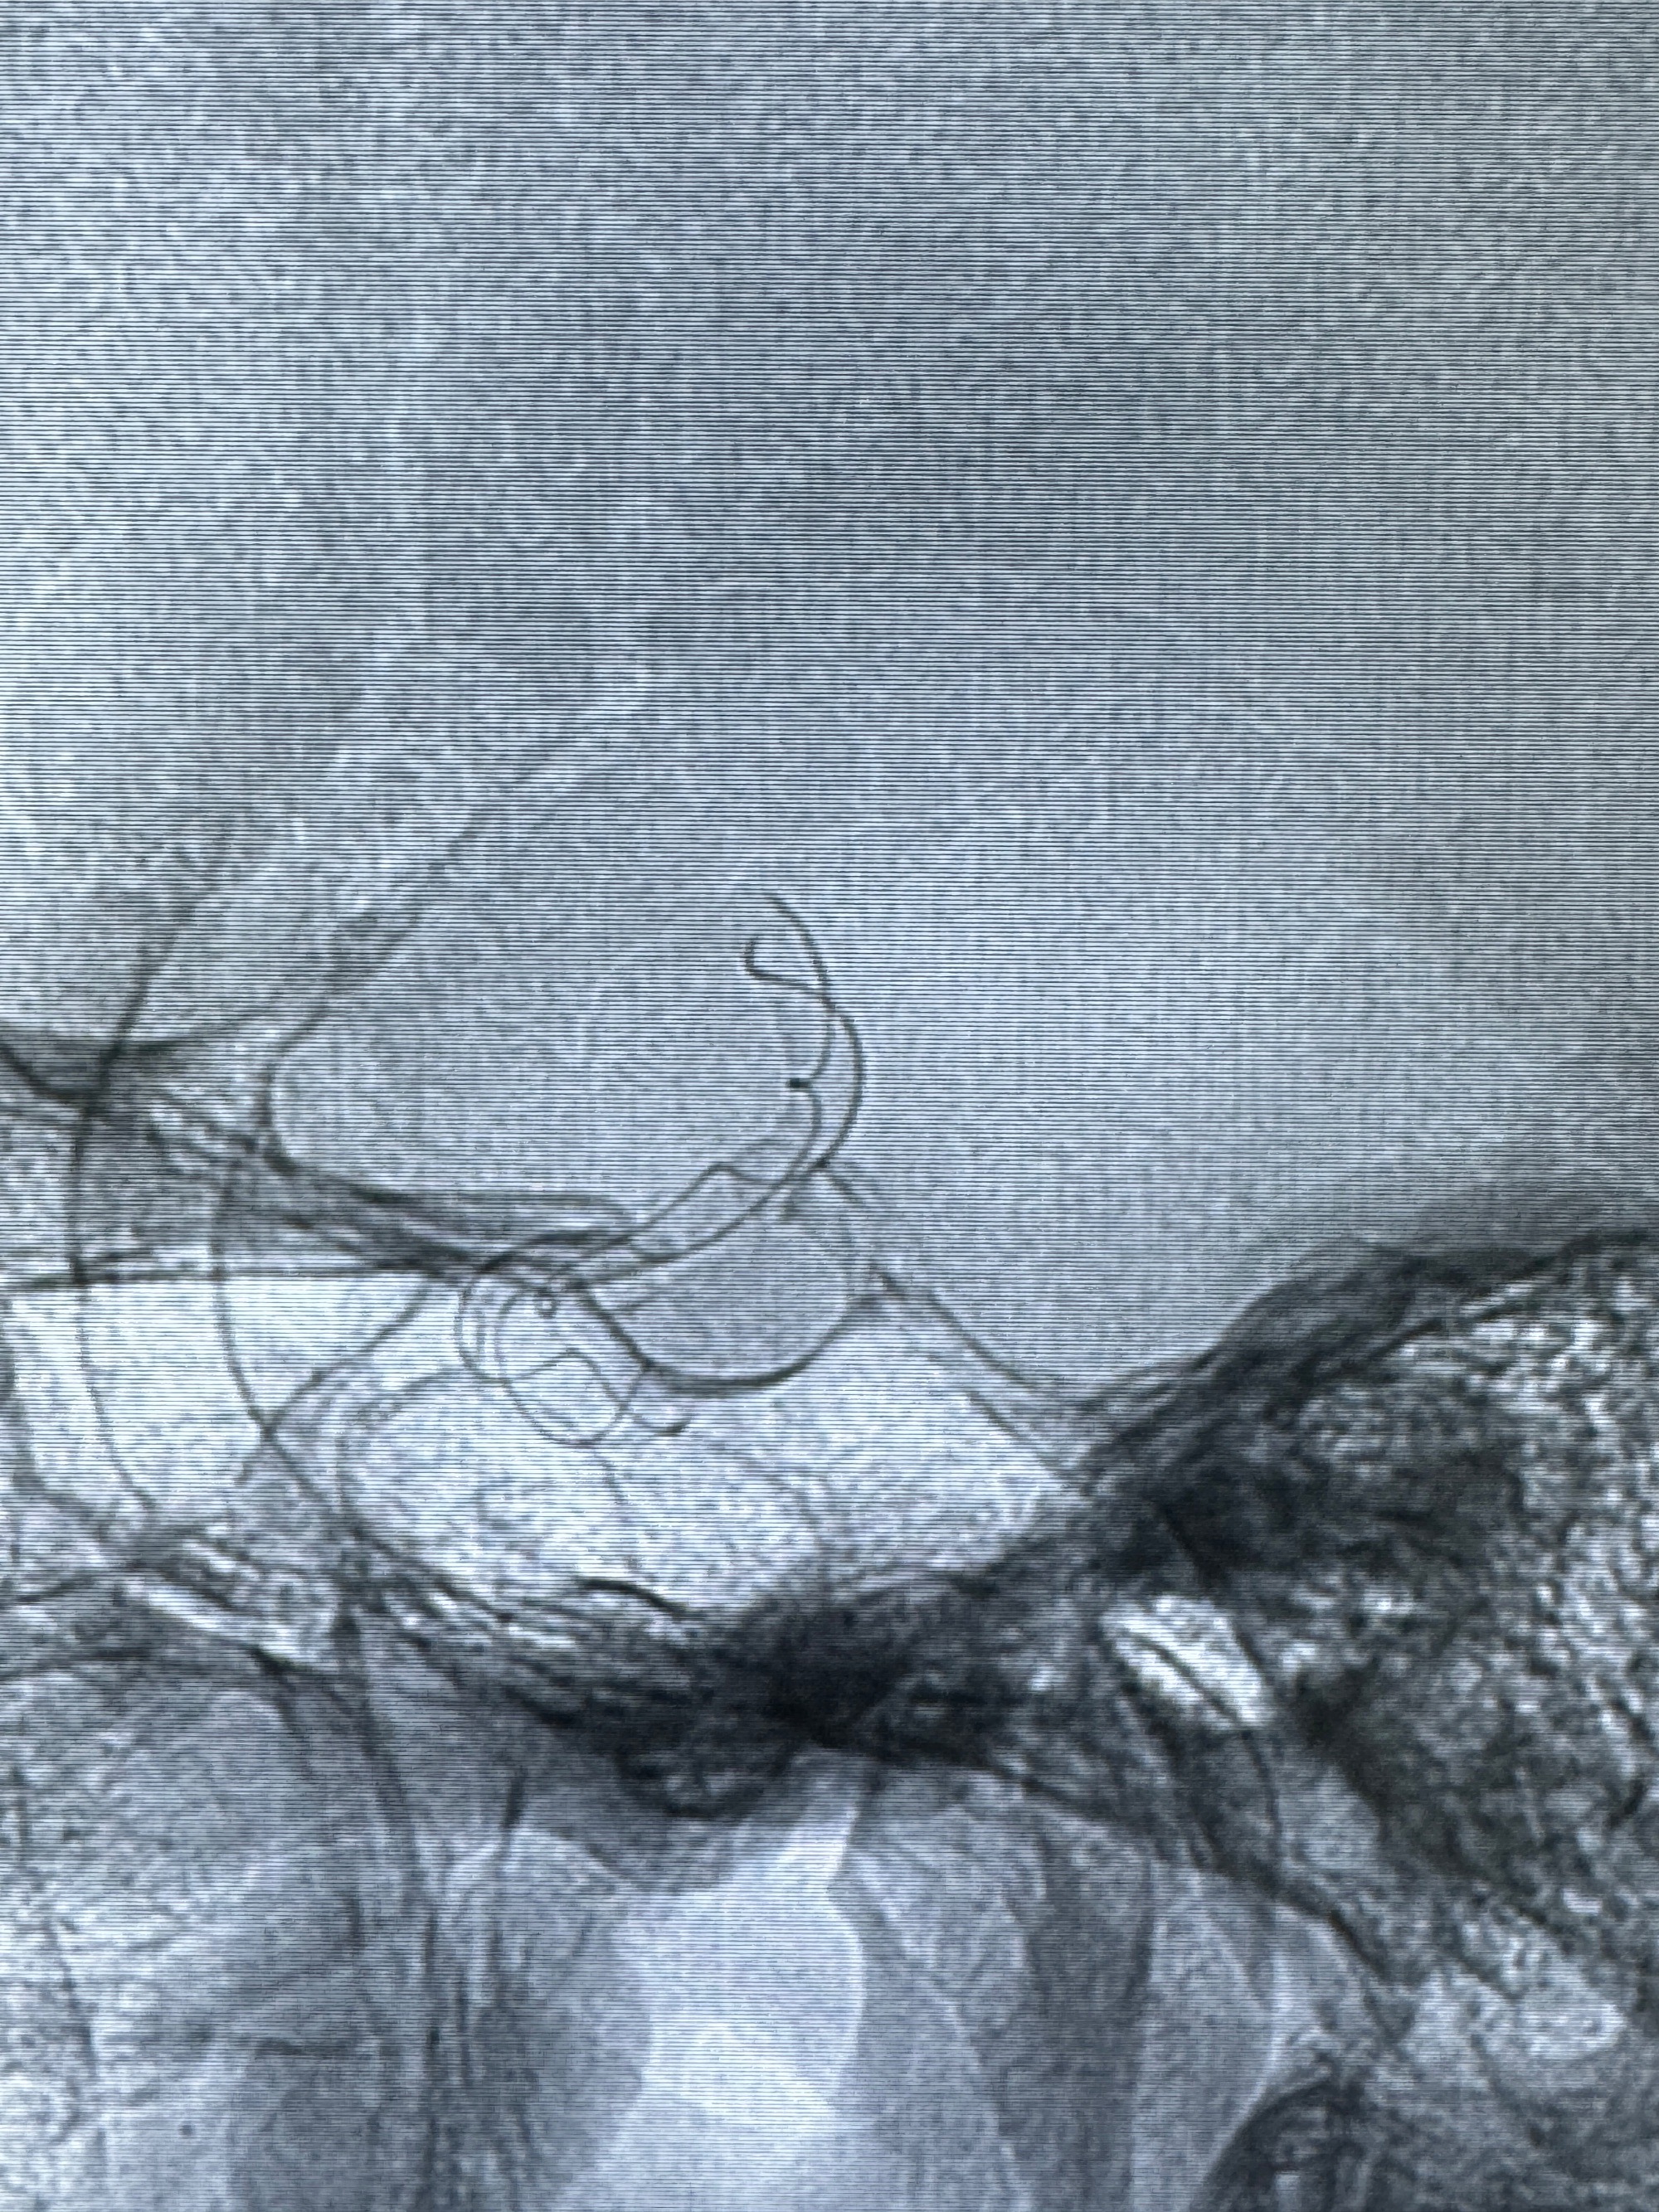

透视可见红圈部分为支架导管的头端

手推冒烟显示支架位置及展开情况,箭头为支架导管的位置

尝试回收支架失败,只能考虑释放支架了

逐帧图像展示歪着脖子释放支架,旁边吩咐助手手机摄影、拍照留像(透视机不能留影像)